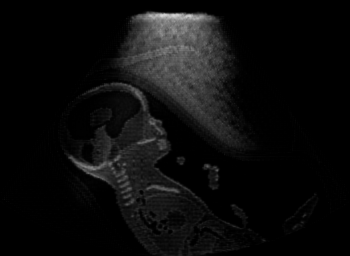

Real in-vivo images. 22 ultrasound sequences were collected using a GE Voluson E8 machine during standard fetal screening exams of 8 patients. Each sequence is several seconds long. We extracted all 4427 frames and resize them to , see Fig. 2 for some examples. The resulting image set was randomly split into training-validation-test sets by a 80-10-10% ratio.